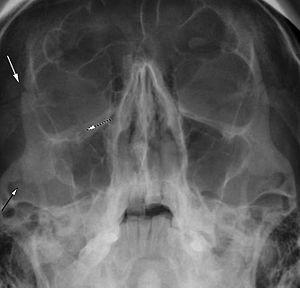

Right zygomaticomaxillary complex fracture with disruption of the lateral orbital wall, orbital floor, zygomatic arch and maxillary sinus.

The zygomaticomaxillary complex fracture, also known as a quadripod fracture, quadramalar fracture, and formerly referred to as a tripod fracture or trimalar fracture, has four components: the lateral orbital wall (at either the zygomaticofrontal suture superiorly along the wall or zygomaticosphenoid suture inferiorly), separation of the maxilla and zygoma along the anterior maxilla (near the zygomaticomaxillary suture), the zygomatic arch, and the orbital floor near the infraorbital canal.